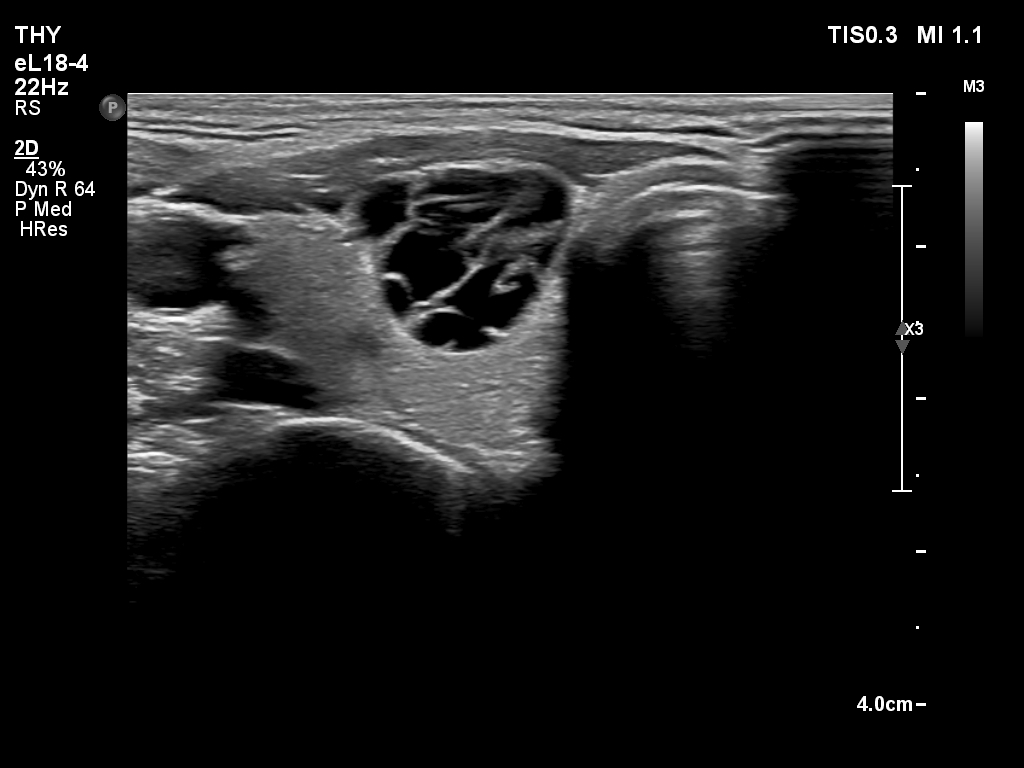

Ultrasonography. The thyroid was echonormal. There was a cystic nodule in the right lobe. The lesion had spongiform portions. The nodules presented all three possible signs of an extrathyroidal extension. There was a minimally hypoechoic nodule in the left lobe.

- The categorization of the cystic nodule depends on the definition of spongiform nodules: the spongiform areas exceeded 50% but the nodule was not entirely spongiform.

- Great proportion of benign nodule presents signs of a possible extrathyroidal extension because these features are non-specific, this is particularly true for cystic nodules located at the edge of a lobe. The liquid produced often bulges the surface of the thyroid. The contour of this nodule was abutting and bulging and the thyroid capsule was discontinuous.